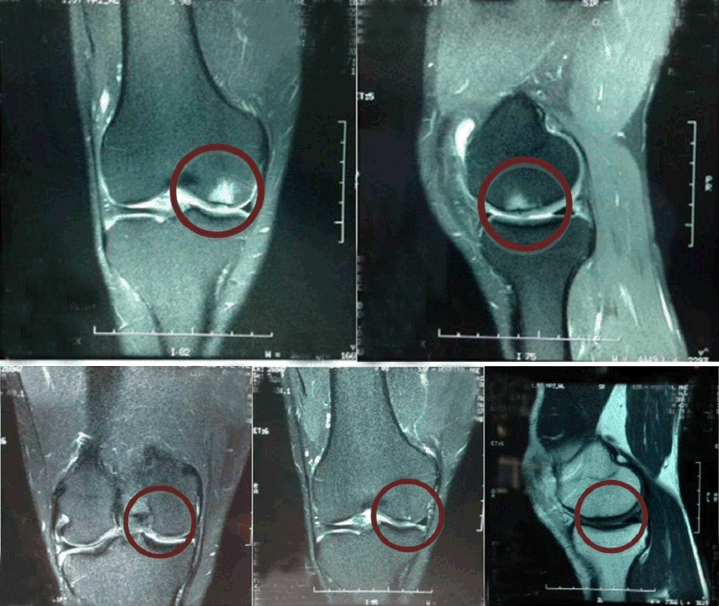

A 42-year-old male farmer, who plays seven-a-side indoor soccer twice a week and jogs three times a week. He sought medical attention due to pain in the right knee and difficulty in walking following a sprain whilst playing indoor soccer. Patient’s body measurements were as follows: 1.75 m, 70 kg and 22.86 kg/m2 of body mass index (BMI). Physical examination showed neutral alignment of lower limbs, pain on the medial joint line and medial femoral condyle during palpation. Limitation of final knee flexion and pain during the McMurray test for the medial meniscus were also detected. All ligament tests were normal, with motion ranges of 0–140 degrees on left knee and 0–115° on the right one. An MRI of the right knee performed a month after his lesion showed deep ulceration on the medial femoral condyle’s weight-bearing cartilage, area with intense reactional bone edema in the spongy section of the femoral condyle, slight strain on the medial collateral ligament, and edema on adjacent soft tissues (Figure 1A).

Final diagnosis was right knee pain due to osteochondral ulceration on the medial femoral condyle. Treatment included physiotherapy and the daily oral intake of 10 grams of collagen hydrolysate Fortigel® dissolved in a glass of water. The patient returned six months later, having undergone 20 sessions of physiotherapy and reporting significant pain reduction. He was counseled to maintain the physiotherapy program, continue the intake of collagen hydrolysate and initiate physical activities to ensure muscle strengthening. In his following consultation, after nine months, the patient was asymptomatic. Physical examination showed a slight weight loss (67 kg), absence of pain, edema or effusion on the joints, and normal range of mobility (0–140°) in both knees. A follow-up MRI scan performed 17 months after his lesion (Figure 1B) showed small, superficial chondral erosions on the medial femoral condyle’s weight-bearing area with significant reduction of the ulcerations formerly detected and without reactional subchondral osteitis.

Figure 1: (A) Note deep ulceration on the medial femoral condyle’s weight-bearing cartilage area (MRI 07/29/2013), (B) Note significant reduction of chondral erosions on the medial femoral condyle’s weight-bearing area (MRI 11/10/2014).